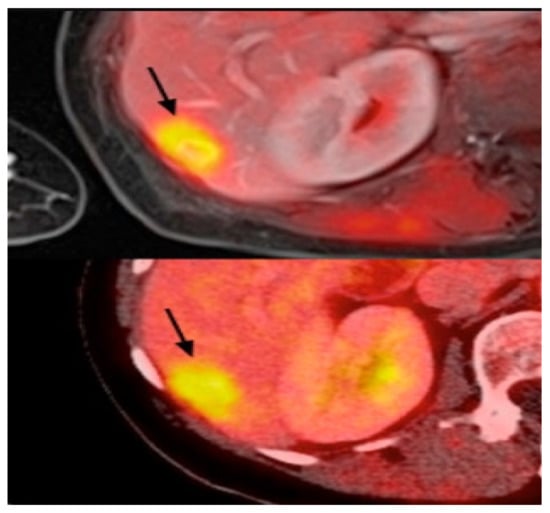

PET uses radiotracers for visualizing and measuring the changes in metabolic processes and other physiological activities, such as blood flow, regional chemical composition, and absorption. PET is a recent effective imaging method showing the promising capability to measure tissues’ in vivo cellular, molecular, and biochemical properties (Figure 6). One of the key applications of PET is the analysis of breast cancer [110]. Studies highlighted that PET is a handy tool in staging advanced and inflammatory breast cancer and evaluating the response to treatment of the recurrent disease [34,35]. In contrast to the anatomic imaging method, PET highlights a more specific targeting of breast cancer with a larger margin between tumor and normal tissue, representing one step forward in cancer detection besides anatomic modalities [111,112,113]. Thus, the PET approach is used in hybrid modalities with CT for specific organ imaging to encourage the advantages of PET and improve spatial resolution, which is one of this modality’s strengths. Additionally, PET uses the integration of radionuclides with some elements or pharmaceutical compounds to form radiotracers, improving the performance of PET [114]. Fluorodeoxyglucose (FDG), a glucose analog, is most commonly used for most breast cancer imaging studies as an effective radiotracer developed for PET imaging [115]. Recent studies clarified a specific correlation between the degree of FDG uptake and several phenotypic features containing a tumor histologic type and grade, cell receptor expression, and cellular proliferation [116,117]. These correlations lead to making the FDG-PET system for breast cancer analysis such as diagnosis, staging, re-staging, and treatment response evaluation [111,118,119]. Another PET system is a breast-dedicated high-resolution PET system designed in a hanging breast imaging modality. Some studies demonstrate that these PET-based modalities can detect almost all breast lesions and cancerous regions [120]. Table 1 summarizes some of PET-based imaging modalities’ limitations and advantages. Also, in Table 2, we provided most commonly used public datasets for different imaging modalities in breast cancer detection.

Figure 6.

Example of PET images for breast cancer analysis [118]. Reprinted/adapted with permission from [118]. 2021, Elsevier.